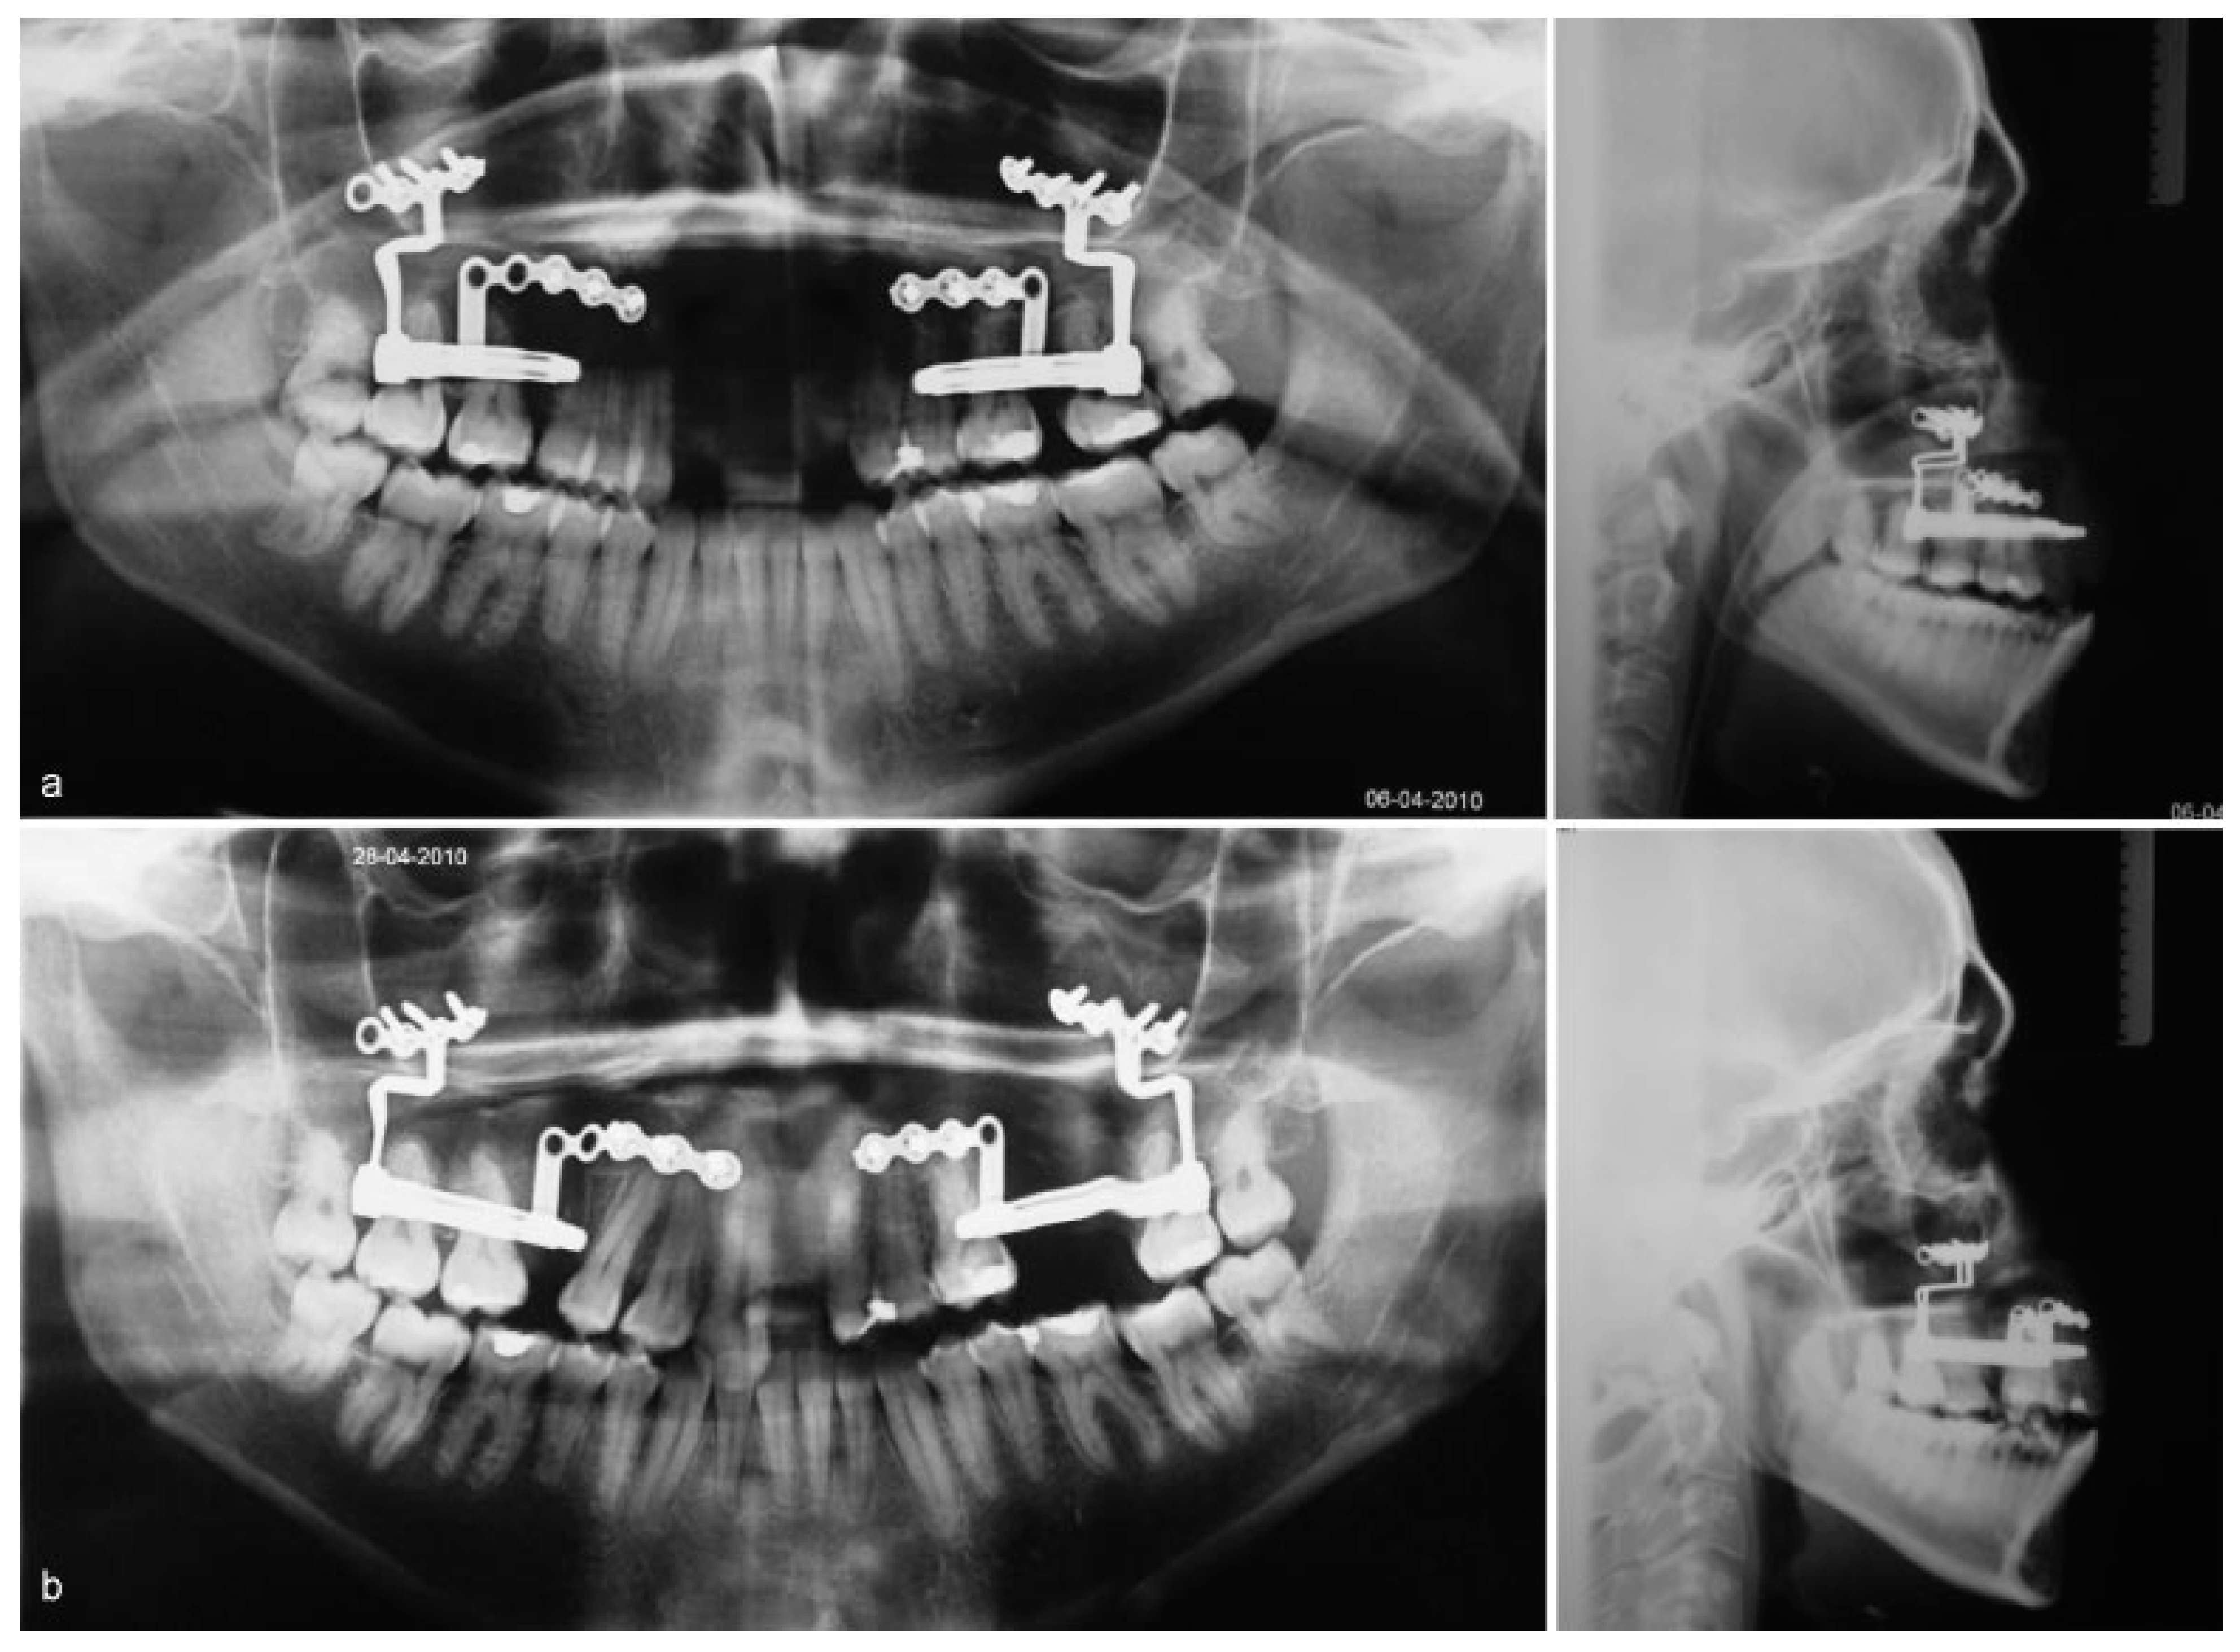

After 5 days’ latency period, activation of the devices started at a daily rate of 1 mm. Both devices achieved full activation, 25 mm on the left and 20 mm on the right, with good stability and maintenance of the planned vectors as shown by the perfect superimposing of devices on the profile radiograms (Figure 4a,b).

Figure 4. (a) Panoramic and profile radiographs at the beginning of distraction phase with distractors symmetrically placed. (b) Panoramic and profile radiographs at the end of distraction phase with both devices still symmetrical after 2.5 and 2.0 cm of distraction.